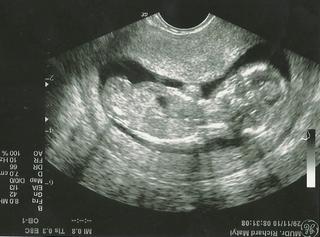

@milka2008 Ahoj moja, momentalne si asi na koze 😉 verim ze vsetko je ok. Ani mi nehovor o tom pocasi, jedna katastrofa. Vcera ma tak bolelo podbrusko ze dovi, takze som sa dost bala. Ale uz to mame za sebouuuuuuuuuuuuuuuuuuuuuuuuuuuuuuuuuuuuuuuuuuuuuuu bola som hned na 7.30hod a sla som ako prva a vsetko je v poriadku. Doki pekne krpca pomeral a vsetko mi poukazoval,nozicky,rucky,hlavicku,ocka,zaludok,stehienka,brusko,plny mocovy mechur no proste vsetko.Vsetky merania mame uplne ukazkove.Zodpovedajuce 13tt. Sijove prejasnenie je uplne v poriadku norma je nejak do 3mm a my nemame ani 1mm, takze super. Placentu mam tiez v poriadku aj krcok takze super. Zaver je taky ze bez VVCH(vrodenych vyv.vad)Taka som stastnaaaaaaaaaaaaaaaaaaaaaaaaaaaaaaaaaaaaaaaa 🙂

Nase male "jéčko" ako ho volame (lebo mam priezvisko Jelinek) sa krasne hybalo, ale sa mu velmi nepacilo ze sa nanho pozerame, sa nam otacal 😀 Tak som skusila zakaslat a sa pomrvil trochu, tak mi doki musel postiskat podbrusko a s nim natriasalo, tak sa chudak zacal viac hybat a zacal sa hrat s pupocn.snurou. Krpcek bol taky neprebudeny este, ani sa mu nedivim v takom pocasi a tak zrana 🙂